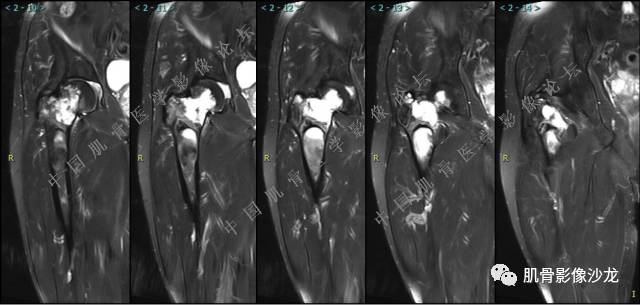

主诉:左髋疼痛1月余

现病史:患者1月余前无明显诱因出现左髋部疼痛,无明显活动受限,当地医院行X线检查,提示左股骨颈异常密度。遂来我院就诊。

既往史:曾患乙型肝炎,未正规治疗,目前无症状。

葛英霖 20:54 @肌骨沙龙义工胡俊华 你确定里面有脂肪?

葛英霖 20:5 4 常规纤维类的多一些,冠状位没有看到明显脂肪。纤维结构不良、纤维组织细胞瘤、软粘纤之类。

夏威夷的风 20:55 大方向纤维类病变

Echo 20:55 考虑纤维类的依据是?

夏威夷的风 20:58 强化渐进性强化吧 边界清晰 里面也见线状低信号

飞鹰行动 21:01 良性纤维组织细胞瘤内部可以有少量脂肪

X(CT、MR)战警 21:01 泡沫细胞被吞噬后形成脂肪信号, bfh可以有脂肪条带样改变

Echo 21:04 总之这例就是各位老师说的硬化边明显,没有软组织肿块,没有侵犯,考虑良性病变,增强渐进性强化,所以考虑BFH